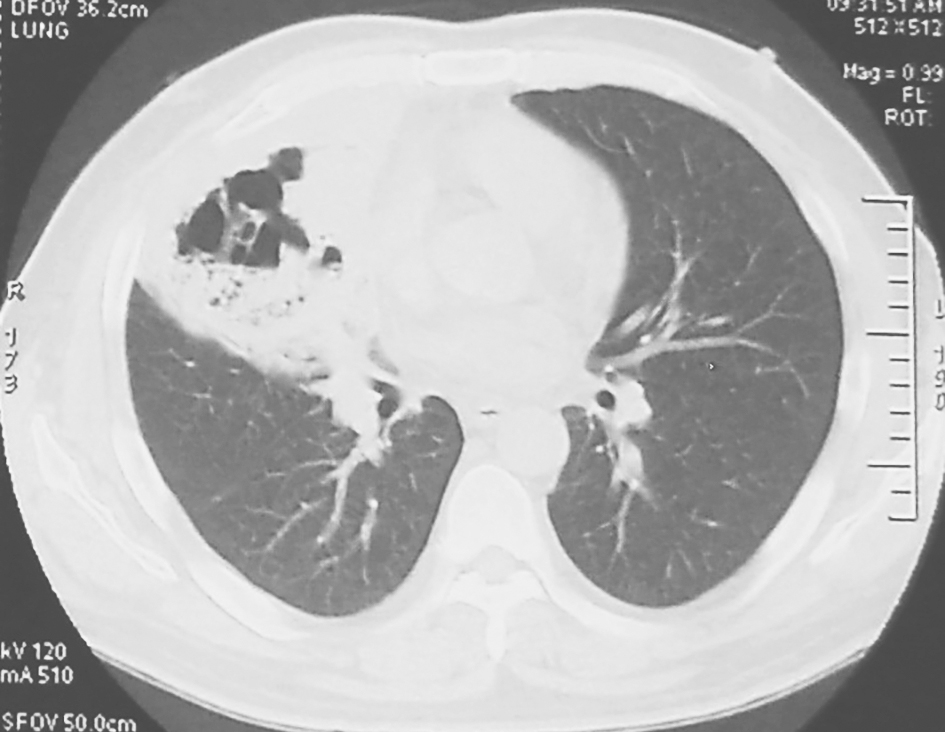

患者起病至住院前的系列胸部CT见图1~图3。

图3 胸部CT表现(2011-02-09)

胸部CT可见右肺实变影较前增大,并出现不规则厚壁空洞